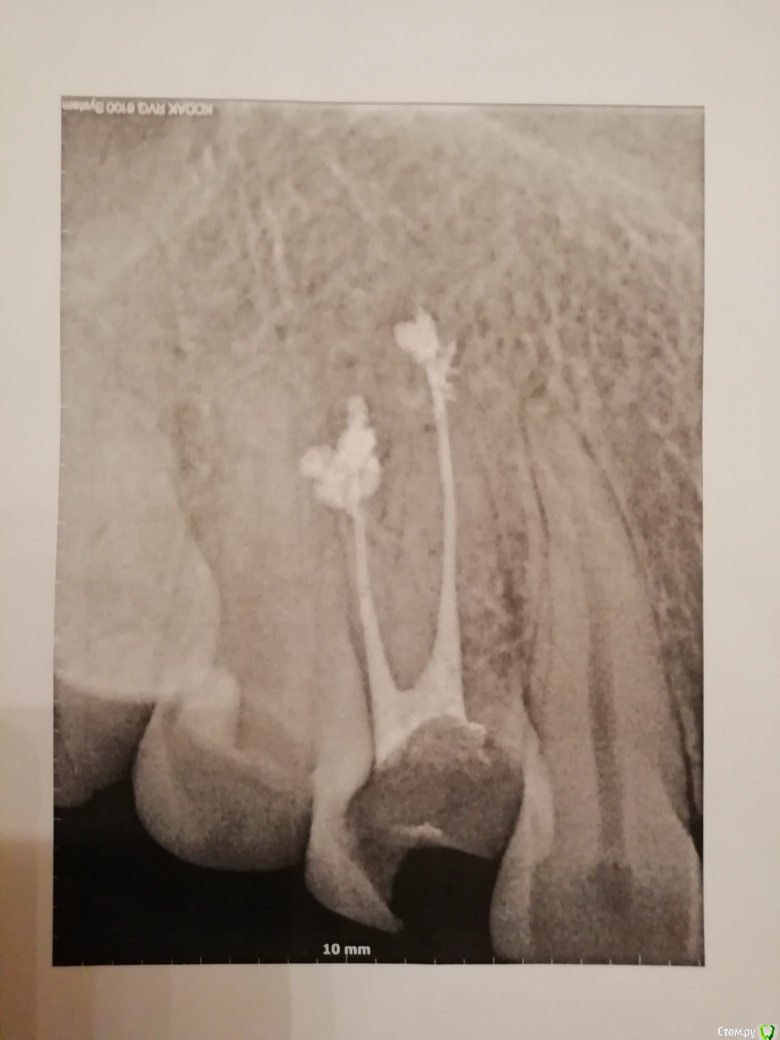

elistac21 Опубликовано 9 января, 2020 Автор Поделиться Опубликовано 9 января, 2020 В продолжение темы. Была сегодня у ортопеда, который мне ставил коронку, по поводу ее снятия для дальнейшего лечения кисты. Сделал еще снимок и сказал, что каналы не перелечить и зуб нужно удалять. Скажите, по снимкам, у зуба нет шансов? Снимки - 3 января в одной клинике, куда обратилась с болью и флюсом, и в другой клинике старый 2010 г (без коронки) и сегодня, 9 января. Ссылка на комментарий